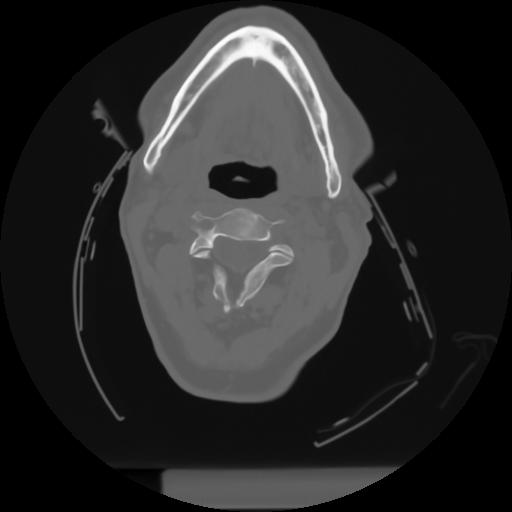

10 P.BLANDAS,,Axial,2.0,P.BLANDAS,,